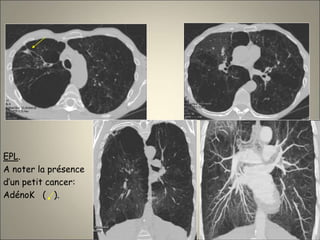

EPL.

A noter la présence

d’un petit cancer:

AdénoK ( ).